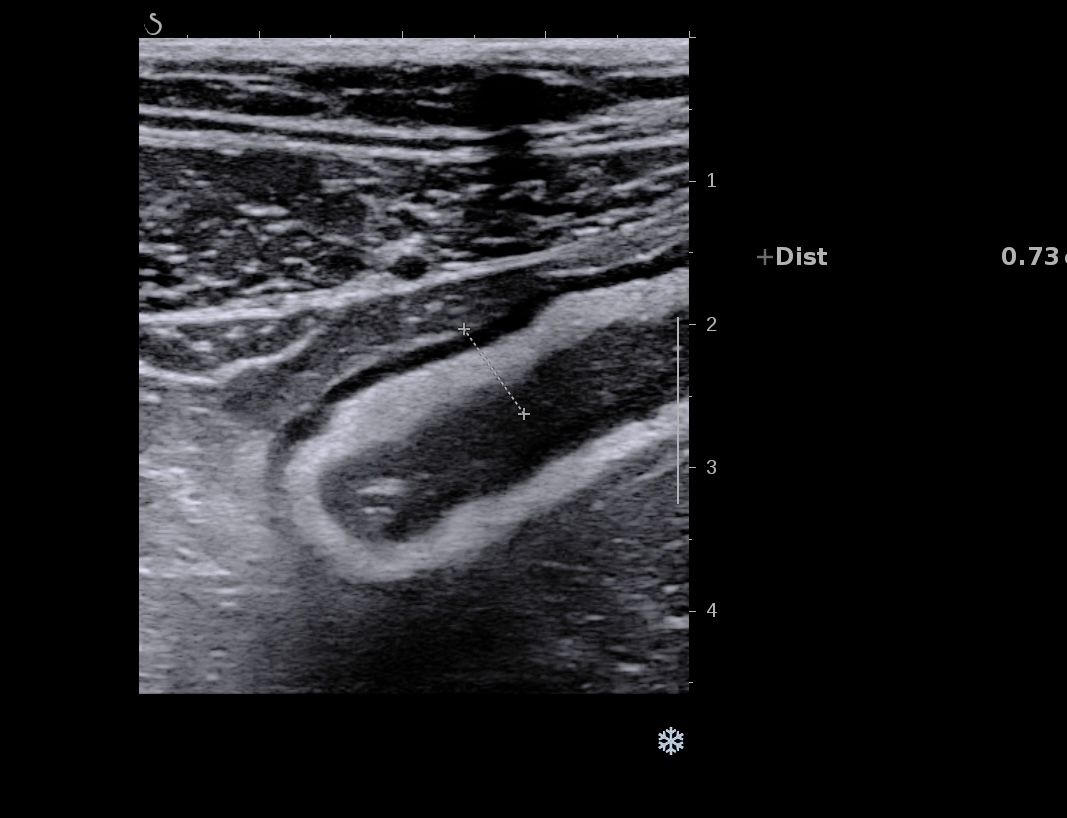

Film en haute fréquence du sigmoïde

Sigmoïde coupes transversales et longitudinales haute fréquence

Sigmoïde coupes transversales et longitudinales et doppler haute fréquence

Ci-dessus, images de la paroi du sigmoïde avec la sonde haute fréquence. On a toujours les mêmes caractéristiques

La graisse est peu infiltrée, Doppler plus marqué (Limberg 2 voir 3)

Le score de Milan est de (4,5 x 1,4+2)= 8,3 donc la maladie reste active, elle s'est même dégradée. (Score passé de 5.74 à 8.3)